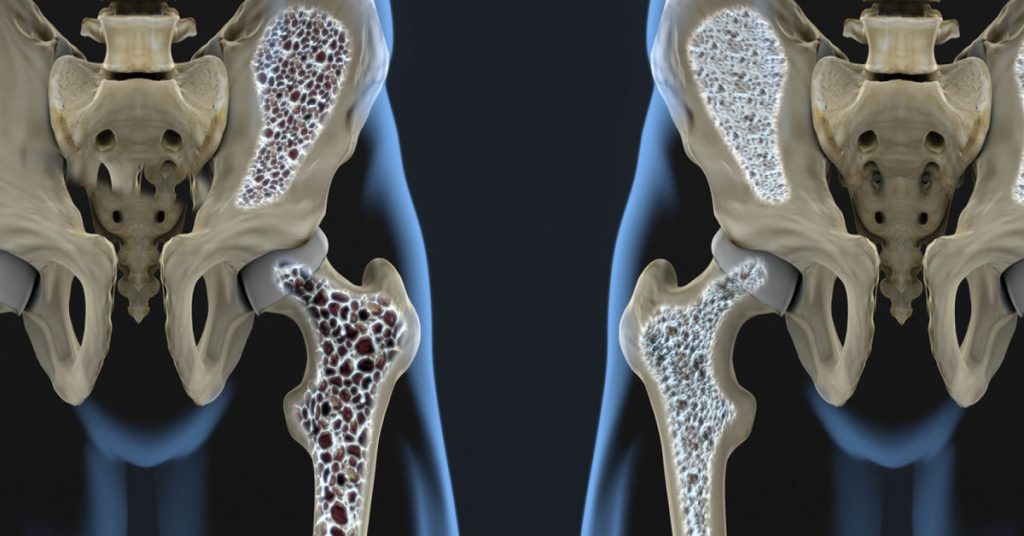

Kemik erimesi, tıbbi adıyla osteoporoz, kemik yoğunluğunun azalması sonucu ortaya çıkar. Kemik yapısı zamanla zayıflar. Kemikler daha kırılgan hale gelir ve küçük travmalar bile kırıklara yol açabilir. Bu noktada kemik erimesi nedir? sorusu özellikle ilerleyen yaşlarda daha sık gündeme gelir. Hastalık çoğu zaman uzun süre belirti vermeden ilerleyebilir.

Kemik yapısı yaşam boyunca sürekli yenilenir. Ancak ilerleyen yaşla birlikte kemik kaybı artabilir. Kemik yoğunluğu azaldığında kemikler daha kırılgan hale gelir. Bu durum çoğu zaman erken dönemde fark edilmez. Hastalar genellikle kırık oluşana kadar belirti yaşamayabilir. Günlük yaşam sırasında küçük düşmeler bile ciddi kırıklara yol açabilir. Bu nedenle kemik sağlığını korumak erken dönemde önem taşır.

İleri yaş döneminde hastalık sessiz şekilde ilerleyebilir. Omurga, kalça ve el bileği kırıkları en sık görülen sorunlar arasındadır. Boy kısalması ve sırt ağrısı da görülebilir. Bazı kişilerde duruş bozukluğu ortaya çıkabilir. Hastalık ilerledikçe omurgada çökme kırıkları oluşabilir. Bu durum günlük yaşam aktivitelerini zorlaştırabilir. Bu nedenle erken tanı ve düzenli kontroller, kemik erimesi riskinin kontrol altında tutulması açısından büyük önem taşır.

Kemik yoğunluğu yaşam boyunca değişiklik gösterebilir. Özellikle yaş ilerledikçe kemik kaybı artabilir. Kemik yapısının zayıflaması kırık riskini yükseltir. Bu durum çoğu zaman erken dönemde fark edilmez. Günlük yaşam sırasında küçük düşmeler bile ciddi sonuçlara yol açabilir. Bu nedenle kemik sağlığını korumak her yaşta önemlidir.

İleri yaşta görülen kırıkların önemli bir nedeni kemik erimesi olabilir. Özellikle kalça, omurga ve el bileği kırıkları sık görülür. Bazı kişilerde boy kısalması ve sırt ağrısı ortaya çıkabilir. Duruş bozukluğu zamanla belirgin hale gelebilir. Hastalık ilerledikçe günlük hareketler zorlaşabilir. Bu nedenle erken tanı ve düzenli takip büyük önem taşır. Kemik yoğunluğu ölçümleri risk durumunu belirlemede yardımcı olabilir.